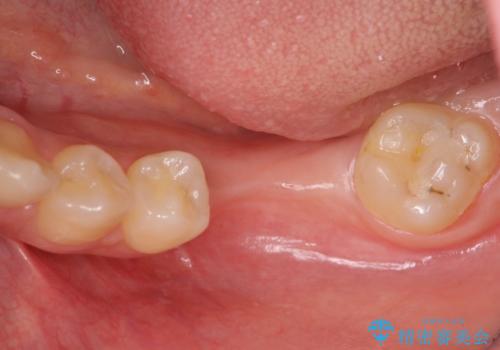

- 他院で抜歯後放置してしまった左下の奥歯の機能・見た目の回復を希望され来院されました。

放置したことによる影響か骨が吸収し、インプラント周囲に十分な骨が確保できないような状況であったため骨造成を併用したインプラント治療を計画します。

インプラントを用いて機能回復を行うことで、奥歯がしっかりと噛めるようになります。